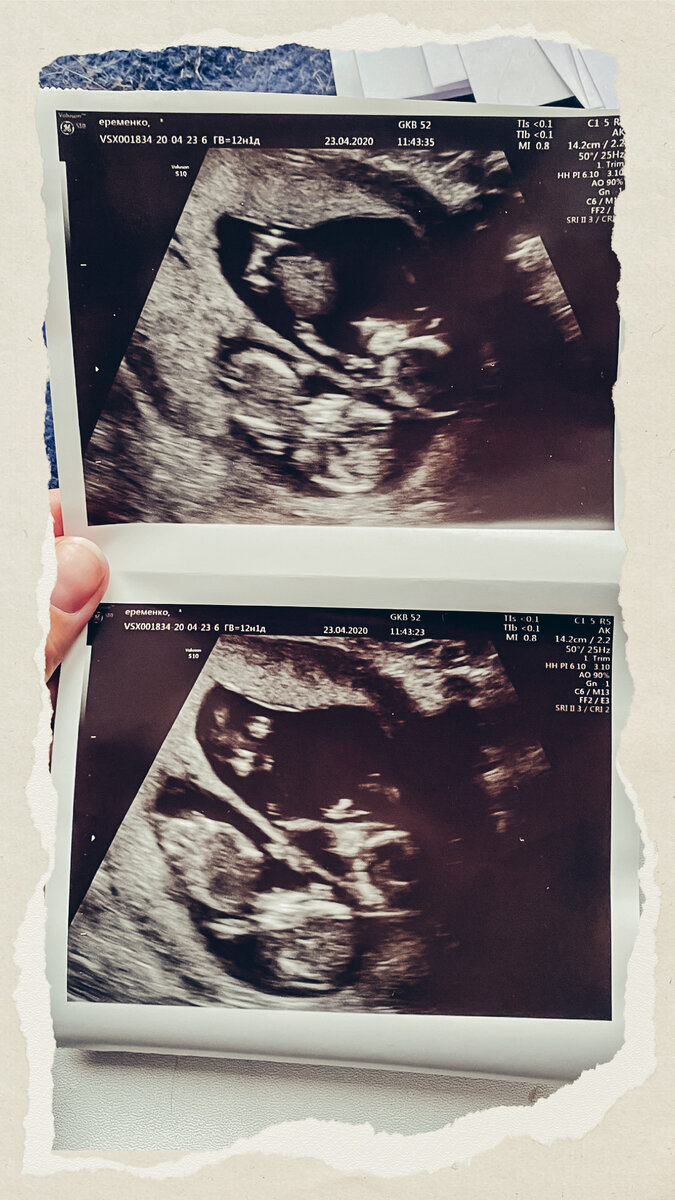

Что смотрят на 1 узи